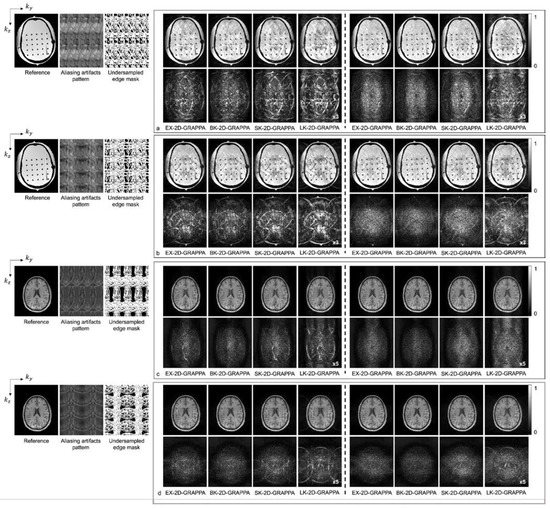

4. Results